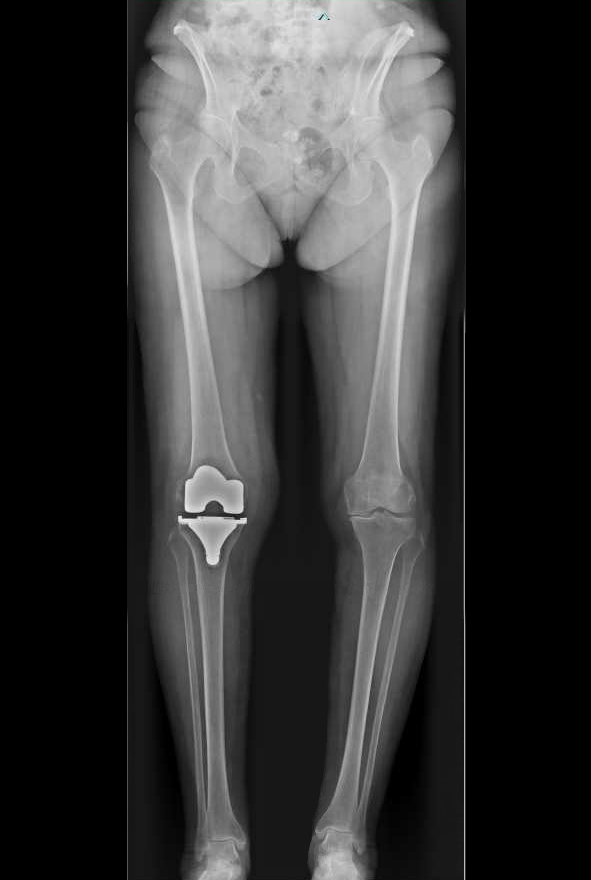

Album photo